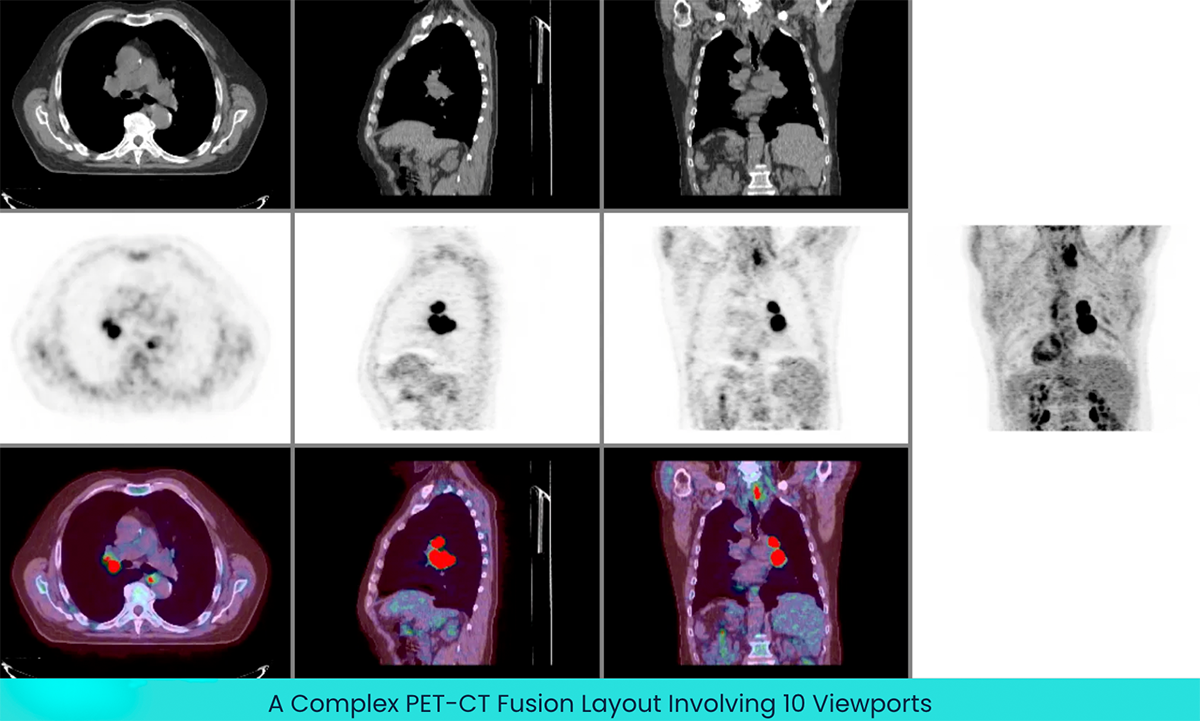

One of the biggest challenges with existing 3D web rendering technologies was the limitation of the number of WebGL contexts that could be created. This meant complex scenarios that required a lot of viewports were out of reach in the web browser. In Cornerstone3D, this problem has been addressed with the introduction of offscreen rendering. This rendering technique allows the Cornerstone3D library to share the same WebGL context across multiple viewports, which enables the ultimate performance of the library with minimum memory footprint. As an example, in the image below a complex PET-CT fusion layout is shown which involves 10 viewports. However, behind the scenes, only one WebGL context drives the 10 displays, with only two 3D volumes in the GPU. Each viewport is derived from the same context (using different camera angles, VOI settings, blendMode, etc.). As you can see, advanced image visualization techniques, such as Multi Planar Reformation (MPR) and Maximum Intensity Projection (MIP), are implemented and available out-of-the-box.